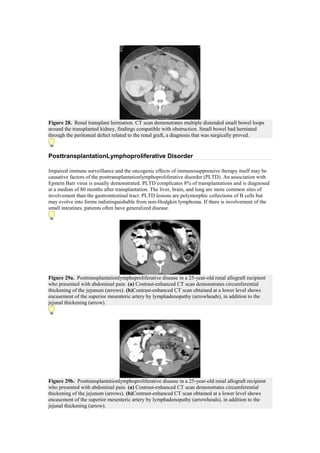

Figure 28. Renal transplant herniation. CT scan demonstrates multiple distended small bowel loops

around the transplanted kidney, findings compatible with obstruction. Small bowel had herniated

through the peritoneal defect related to the renal graft, a diagnosis that was surgically proved.

PosttransplantationLymphoproliferative Disorder

Impaired immune surveillance and the oncogenic effects of immunosuppressive therapy itself may be

causative factors of the posttransplantationlymphoproliferative disorder (PLTD). An association with

Epstein Barr virus is usually demonstrated. PLTD complicates 8% of transplantations and is diagnosed

at a median of 80 months after transplantation. The liver, brain, and lung are more common sites of

involvement than the gastrointestinal tract. PLTD lesions are polymorphic collections of B cells but

may evolve into forms indistinguishable from non-Hodgkin lymphoma. If there is involvement of the

small intestines, patients often have generalized disease.

Figure 29a. Posttransplantationlymphoproliferative disease in a 25-year-old renal allograft recipient

who presented with abdominal pain. (a) Contrast-enhanced CT scan demonstrates circumferential

thickening of the jejunum (arrows). (b)Contrast-enhanced CT scan obtained at a lower level shows

encasement of the superior mesenteric artery by lymphadenopathy (arrowheads), in addition to the

jejunal thickening (arrow).

Figure 29b. Posttransplantationlymphoproliferative disease in a 25-year-old renal allograft recipient